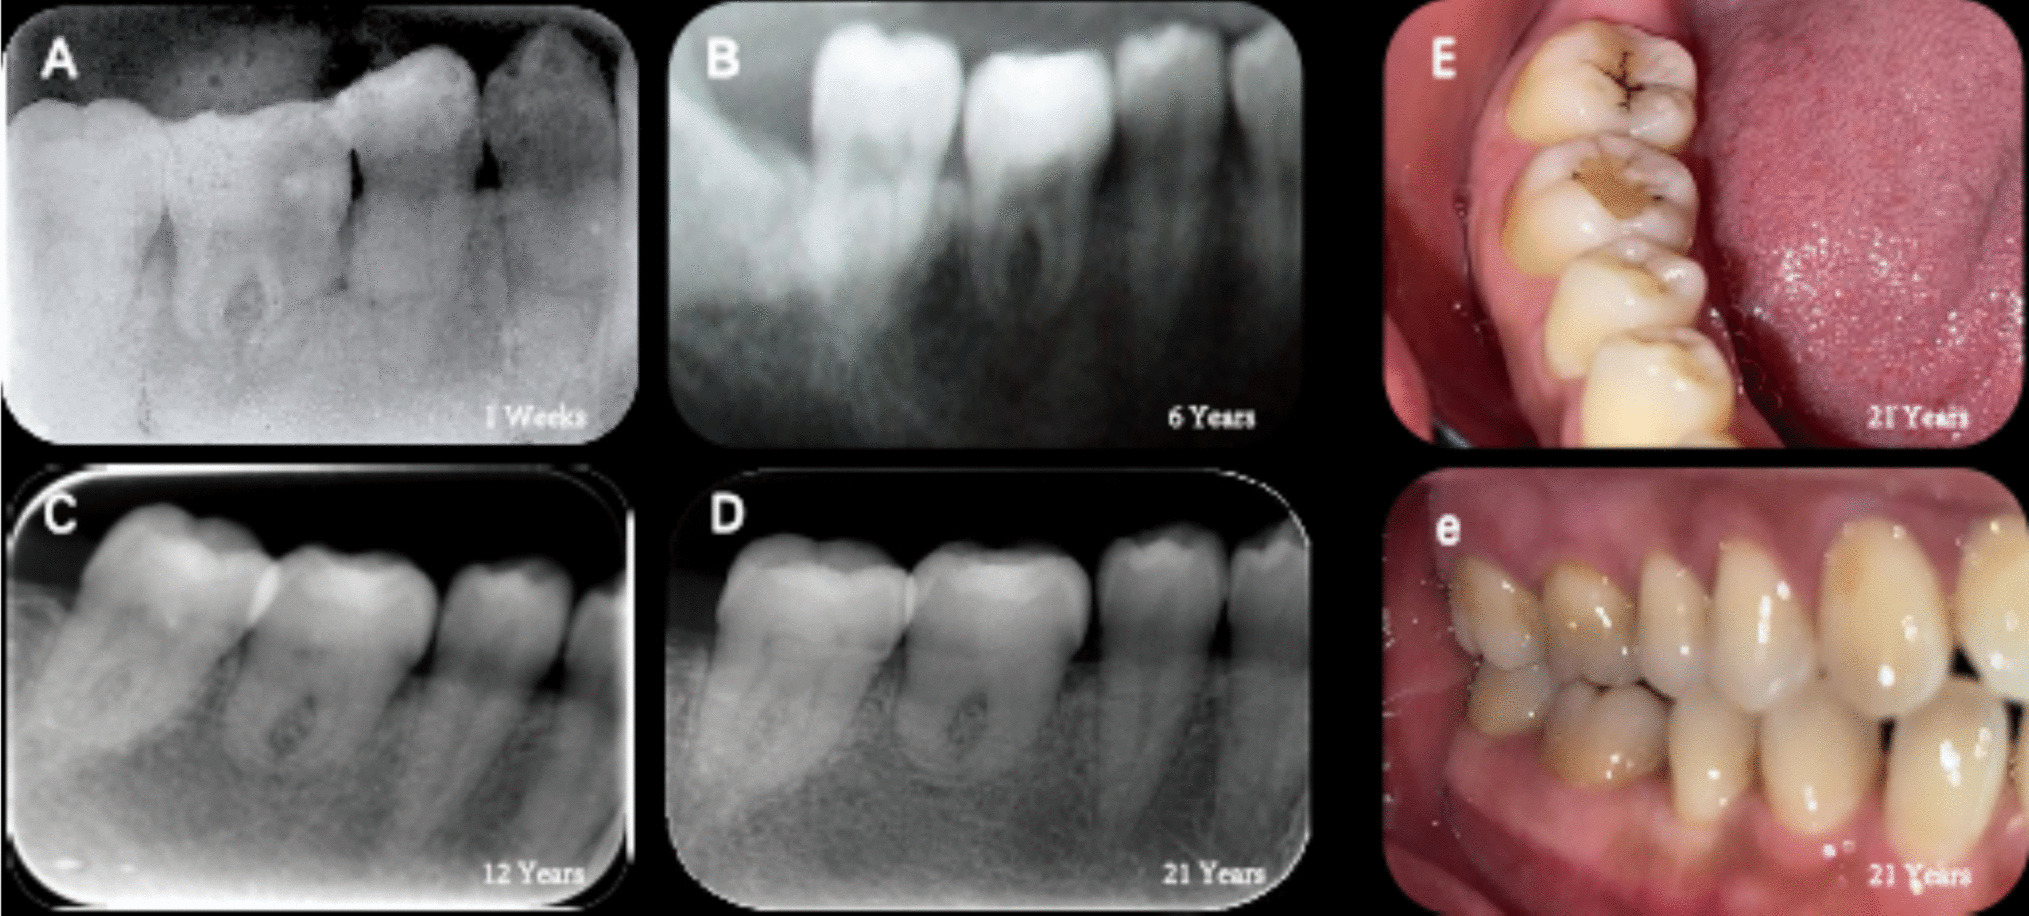

Surgical management and follow up

The surgical procedure was essentially the same as Case 1. The patient was followed up 6 months after transplantation, during which no significant pain or discomfort was reported. Imaging examinations revealed that the transplanted root had begun to form gradually, with the alveolar bone tightly integrated with the root (Fig. 15C). No apparent periapical lesions were observed. Consequently, the fixed ligature wire was removed, and monitoring continued, with RCT planned if necessary.

Fig. 15

A immediate postoperative (apices undeveloped) (B) two weeks postoperative (apices not yet completely closed) (C) six months postoperative (apices developed, distal caries involved.) (D) one year postoperative (apical foramen closed and caries filled.) (E) twenty years postoperative (residual root remained, alveolar socket reconstructed) e: twenty years postoperative (intraoral photograph)

Bild vergrößern

One year later, follow-up evaluations indicated well-developed roots, a tendency for closure of the apical foramen was observed. Throughout this period, the patient experienced no discomfort and demonstrated good proprioceptive function. An intraoral examination and imaging revealed caries in the distal-medial region of the crown, which was restored with a filling (Fig. 15D). Unfortunately, during the patient’s visit 20 years post-grafting, it was noted that the grafted tooth had deteriorated to a stump due to untreated caries (Fig. 15E).